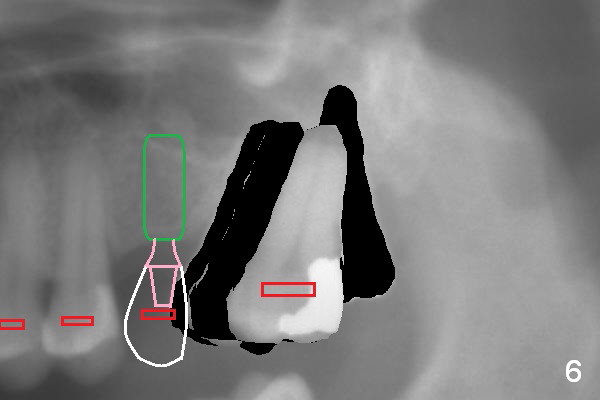

A 44-year-old lady requests restoring missing teeth at #14 (Fig.1 *) and 30. There is no buccopalatal width deficiency at #14, but the mesiodistal space needs to be expanded by distalizing the tooth #15 (arrow) after extraction of the tooth #16 (x). Placement of a longest mini-implant at the tuberosity area after socket healing is anticipated.

When the tooth #15 is distalized (Fig.3), place an implant at #14 (Fig.4 green), parallel to the tooth #13 and extract #16 (black). When the implant osteointegrates, place an abutment (Fig.5 pink), provisional (white) and bracket at #14. The implant is used as an anchorage to further distalize #15 until the latter reaches the normal position (Fig.6). CT study shows how much the tooth movement is needed prior to implantation.